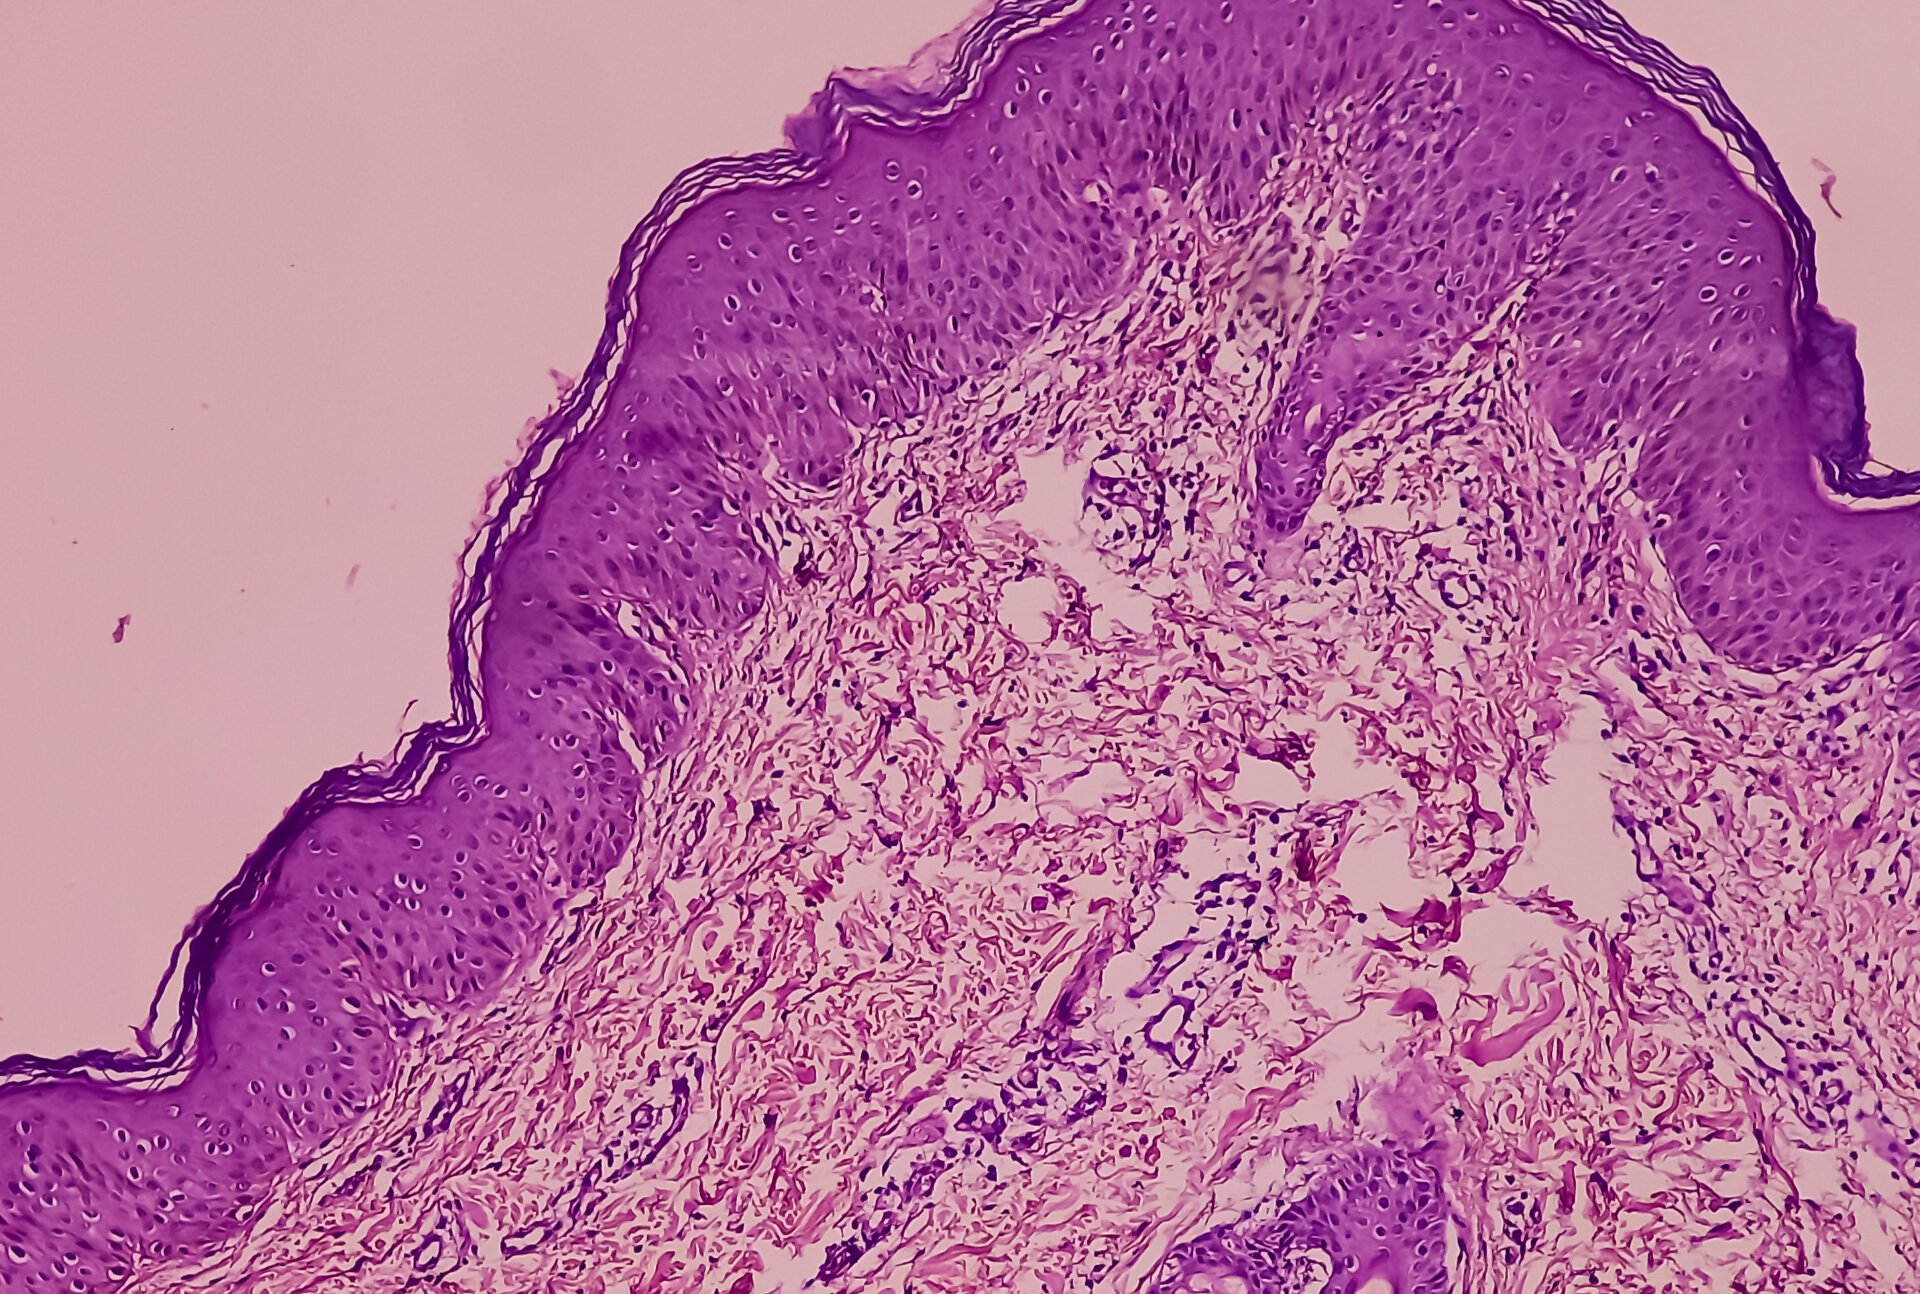

La terapia empírica tuvo éxito

La paciente fue trasladada a la unidad de cuidados intensivos pediátricos el sexto día de la enfermedad debido a la afectación sistémica con cambios cutáneos rápidamente progresivos, acompañados de taquicardia, oliguria y necesidades adicionales de oxígeno. El aspirado de médula ósea no mostró malignidad y fue negativo para Leishmania. La biopsia de piel tomada el día 6 mostró signos de FUMHD con dermatitis de interfase y predominio de células T citotóxicas CD8+. La PCR para el SARS-CoV-2 fue negativa en la biopsia cutánea. El tratamiento empírico consistió en ceftazidima, vancomicina, doxiciclina, anfotericina B liposomal e inmunoglobulinas intravenosas (2 g acumulativos por kg de peso corporal los días 6 y 7). El paciente recibió oxígeno y diuréticos adicionales y se le mantuvo en respiración espontánea. El tratamiento tópico de la piel consistió principalmente en preparados tópicos que contenían urea y triclosán. Con estas medidas, el estado de la paciente mejoró continuamente sin tratamiento inmunosupresor sistémico. Fue trasladado a la sala normal el día 11 y dado de alta el día 18. En ese momento, su principal queja seguía siendo la discapacidad visual debida a la afectación corneal. Retrospectivamente, el estado de la paciente se interpretó como FUMHD, posiblemente desencadenada por una infección por micoplasma. Seis meses después del episodio de FUMHD, la paciente se ha recuperado totalmente sin secuelas relevantes ni reaparición de síntomas dermatológicos.